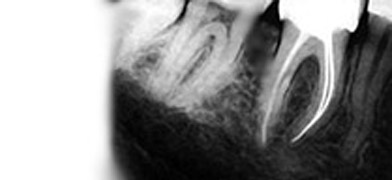

The first step towards a successful endodontic operation is opening the pulp chamber and locating the root canals.